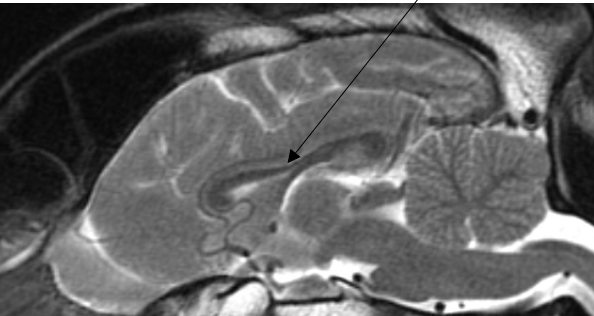

what structure is shown here

corpus callosum

what is the function of corpus callosum

transfer of information

connects forebrain with brain stem

1. corpus callosum: a mass of fibres that connect right and left cerebral hemispheres